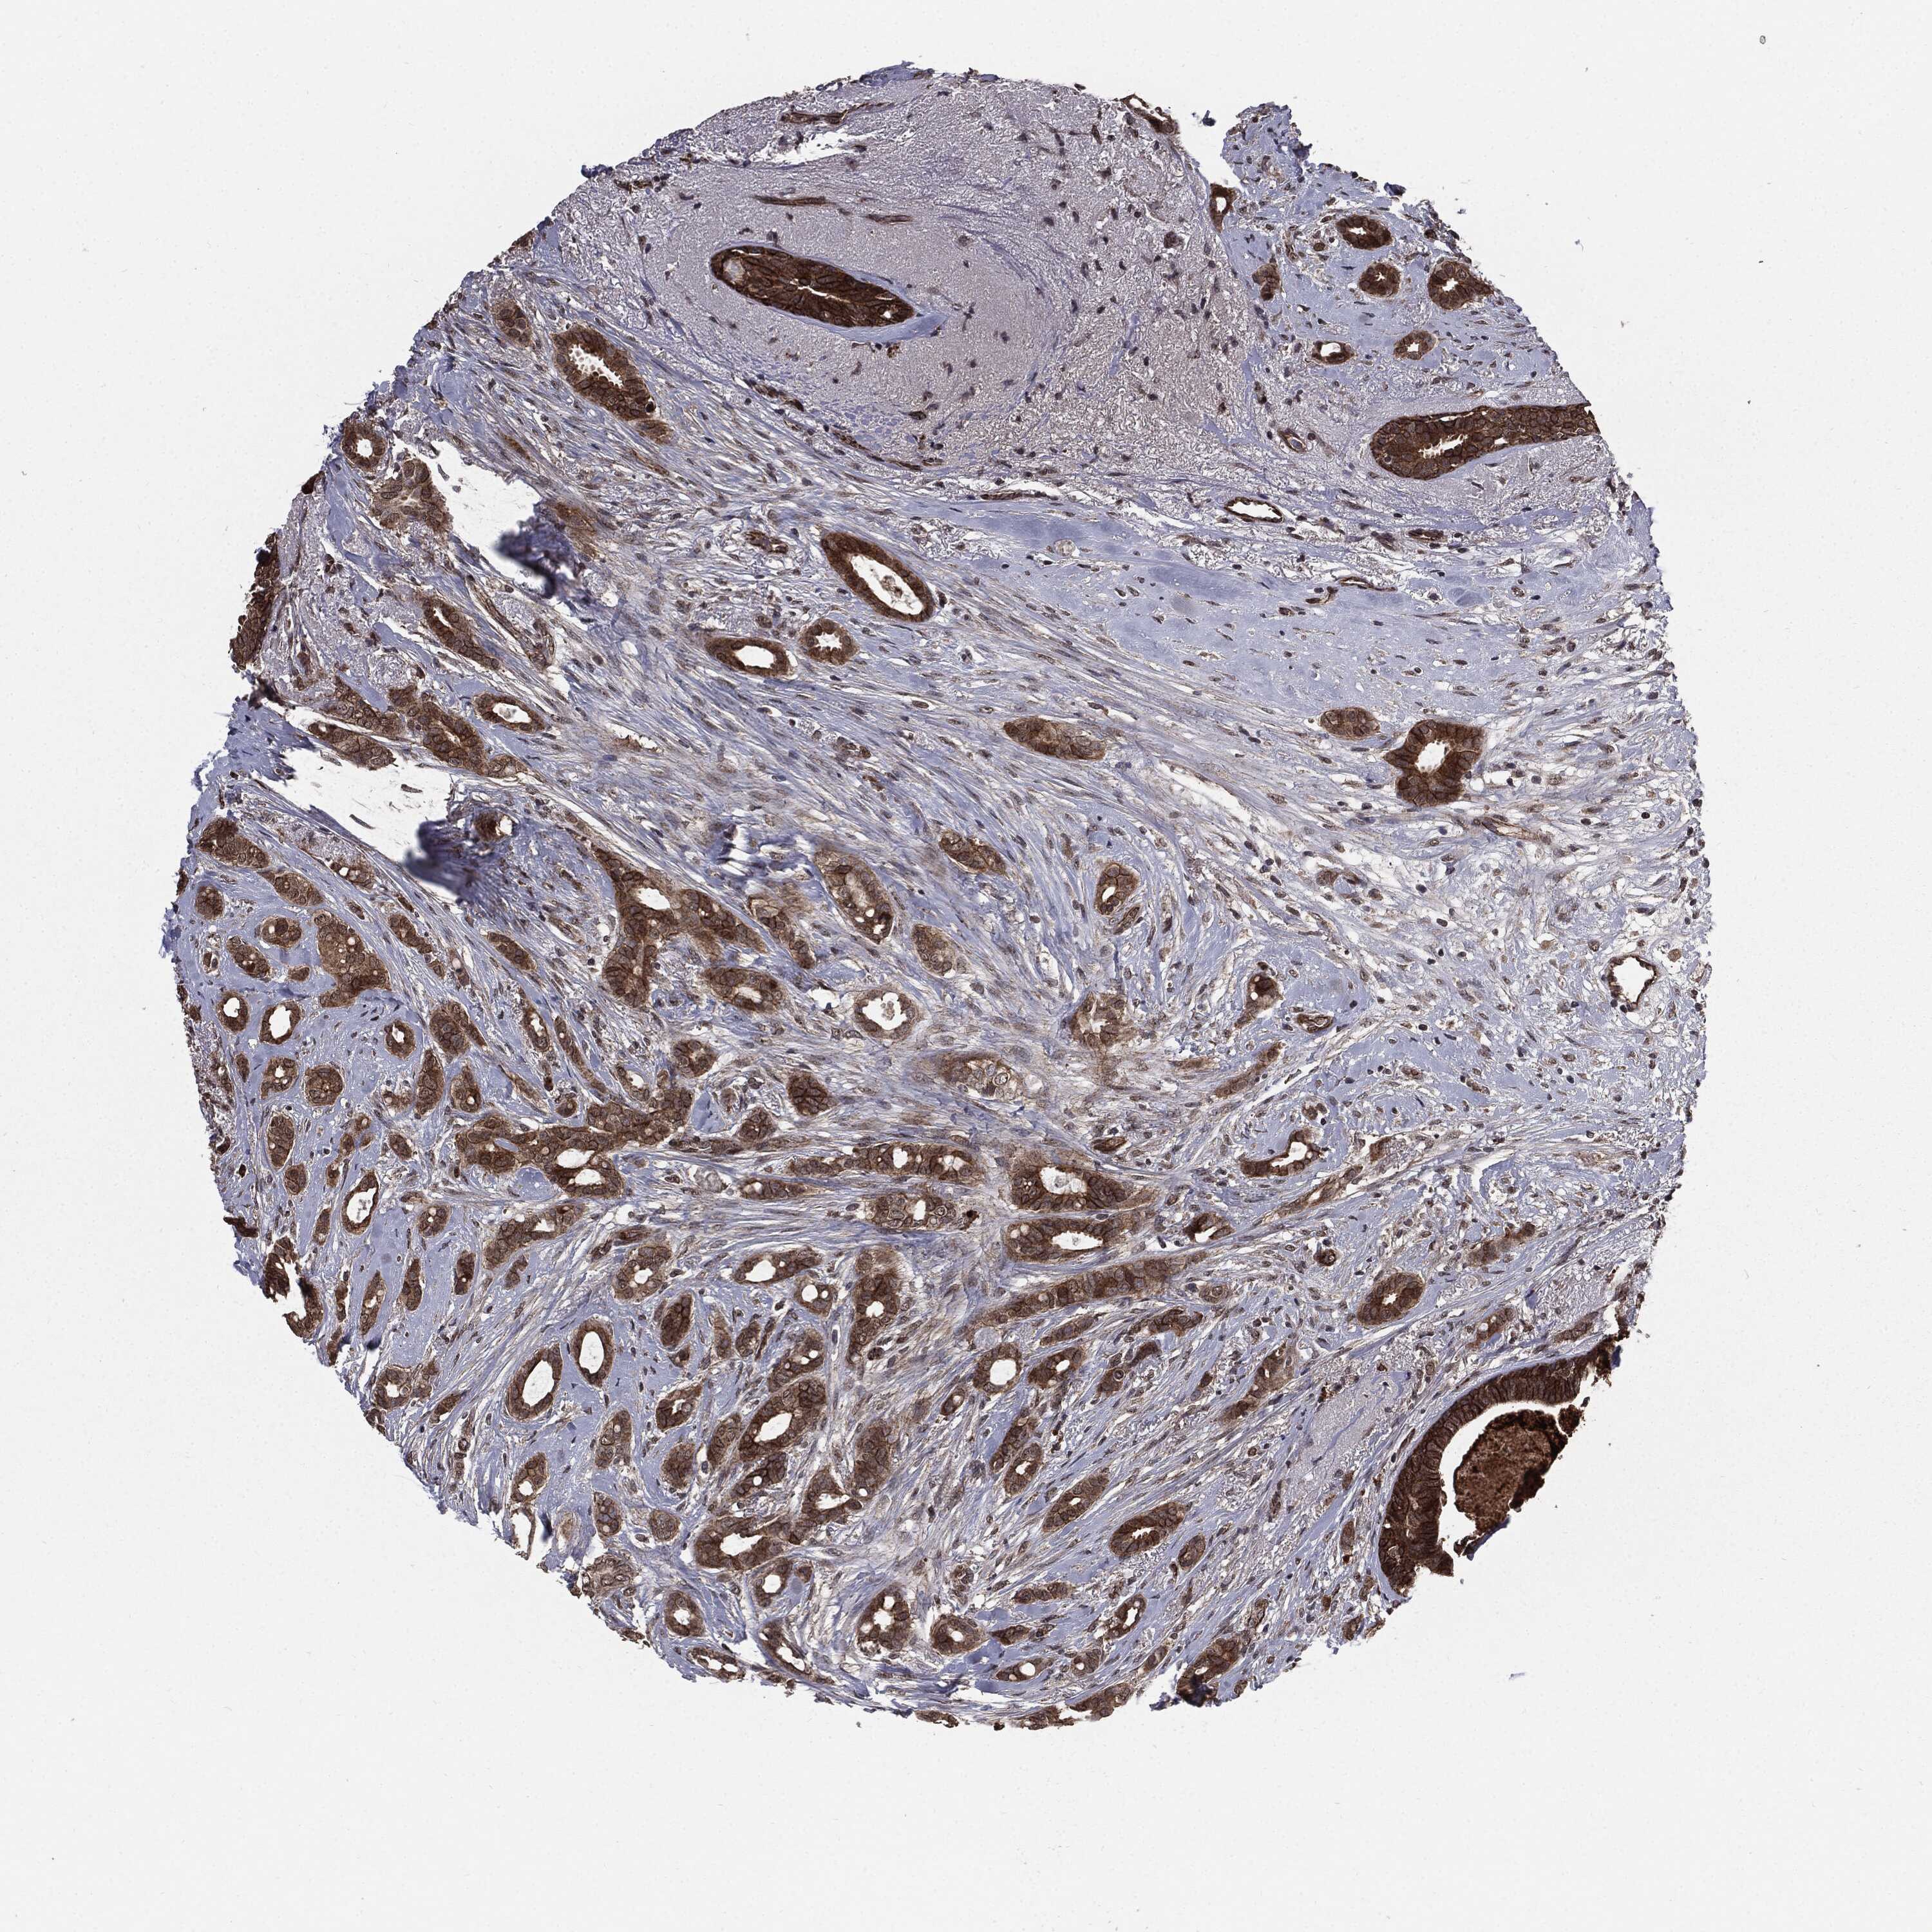

CANCER BREAST CANCER Show tissue menu

BRCA TCGA BRCA VALIDATION PROTEIN EXPRESSION

ANTIBODIES

AND

VALIDATION